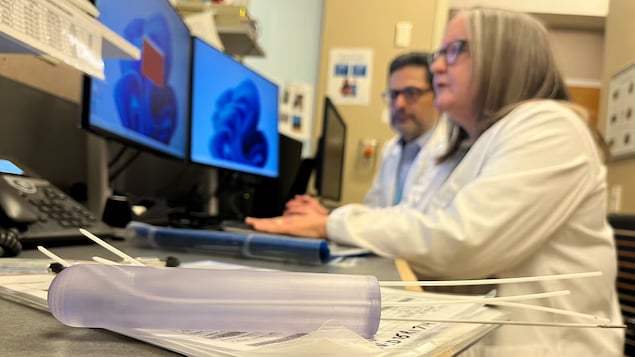

Une imprimante 3D crée un outil adapté au corps de chaque patiente, ciblant les tumeurs avec précision.